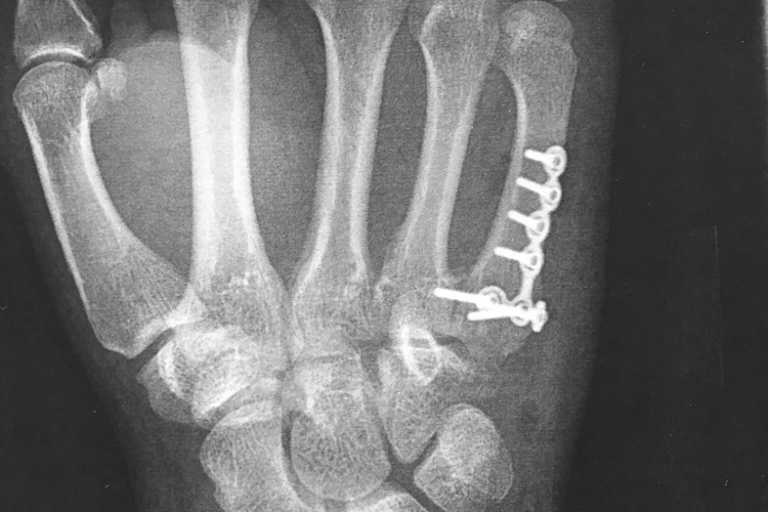

Im Zeittraining zum WM-Lauf hatte es geregnet und Vincon liess es nicht übertrieben schnell angehen. Doch das Sondieren der Streckenverhältnisse ging gerade mal zwei Runden lang. Das Hinterrad ging weg und er flog per Highsider ab. "Der Sturz selber war jetzt nicht so schlimm", erklärt er. "Aber ich bin halt blöd auf die rechte Hand gefallen." Zeit für einen Arztbesuch blieb nicht. "Es war ja Quali", so die einfache Antwort nach dem Warum. "Im Nassen ging es noch ganz gut, als die Strecke abtrocknete war mir schon klar, dass es problematisch werden würde. Meine Zeiten waren nicht hervorragend aber akzeptabel." Der Arztbesuch Anfang dieser Woche brachte dann den Bruch des fünften Mittelhandknochens zu Tage. Ein Bruch, der ohne Operation ca. sechs Wochen zur Heilung benötigt. Zu lang für Dominik Vincon. Er unterzog sich einer ambulanten Operation. "Es wurde dann doch etwas größer", erzählt er. "Aber viel hält viel. Ich will ja in drei Wochen beim Endurance-Finale in Oschersleben dabei sein."